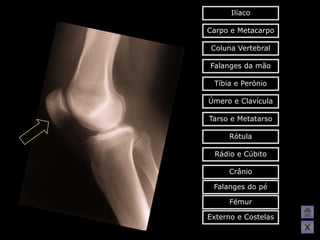

O   Aqui tens de conseguir acertar na

resposta, só assim poderás avançar

para a figura seguinte!!!

Ilíaco Carpo e Metacarpo Coluna Vertebral Falanges da mão Tíbia e Perónio Úmero e Clavícula Tarso e Metatarso Rótula Rádio e Cúbito Crânio Falanges do pé Fémur Externo e Costelas X